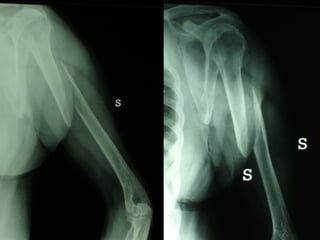

Un’altra situazione di emergenza ortopedica è rappresentata dalle fratture delle ossa lunghe in pazienti con gravi traumi cranici e toracici

Dal Gennaio 2000 al Febbraio 2006 abbiamo trattato 167 fratture chiuse  con placca percutanea  in 164 pazienti :  27 lesioni diafisarie di gamba, 12 piloni tibiali ,  11 fratture prossimali di tibia, 36 fratture sovracondiloidee di femore, 17 fratture diafisarie di femore, 43 fratture metaepifisarie prossimali di omero, 21 diafisarie d’omero.  156 guarigioni 8 fallimenti

Dal Giugno 2002 al Dicembre 2004 abbiamo trattato 5 fratture esposte: 3 di tibia e 2 di ulna 5 guarigioni